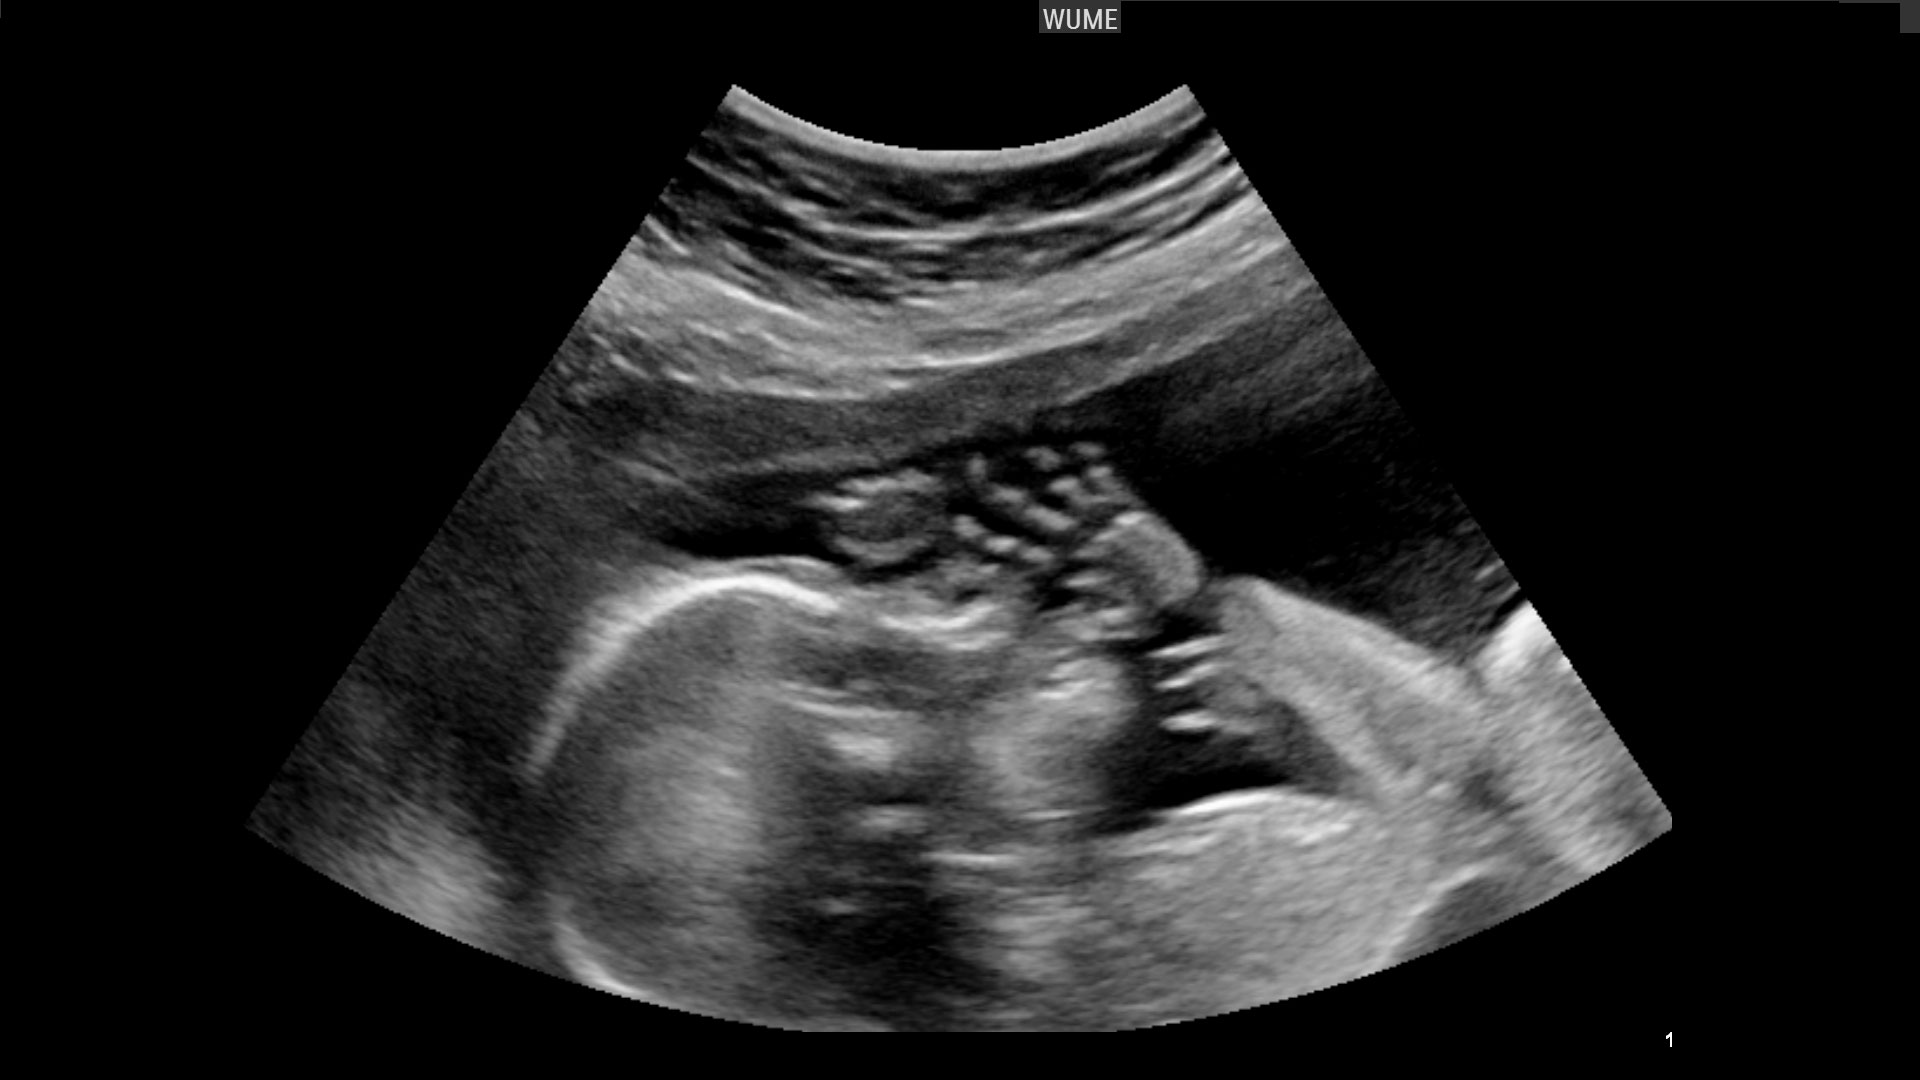

▼雖然當天是星期日婦產科沒有開,可是在姐姐的堅持下,原po跟老公馬上到大醫院掛急診,在測了胎音後醫生表示寶寶心跳很弱,建議馬上剖腹,於是原po就這樣剖腹生產了。她如今還清楚記得,醫生接生到一半時跟助理表示是「臍帶扭轉」。在順利誕下女兒後,醫生也對原po老公表示「這是臍帶扭轉,造成養份無法傳過去給北鼻,如果再慢個1-2天小孩就沒了。」 (示意圖)